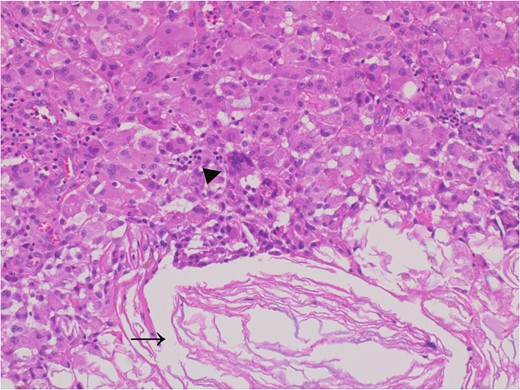

Six core needle specimens containing cystic walls were sampled by core needle biopsy, hematoxylin, and eosin stain, ×2 magnification (Fig. 4A). Cystic wall was lined by mature stratified squamous epithelium with granular layer and did not contain adnexal structure, hematoxylin, and eosin stain, ×20 magnification (Fig. 4B).

The adhesive region revealed keratin (allow) which flowed outside the cyst and granulomatous response for keratin with multinucleated giant cells (allow head), Hematoxylin and eosin stain, ×20 magnification.